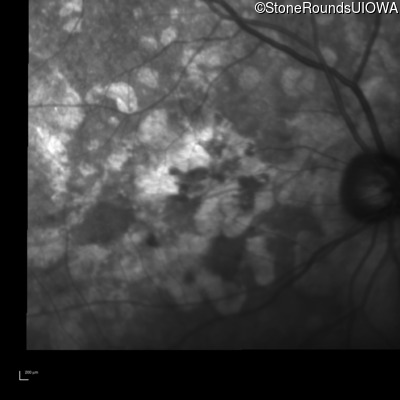

Infrared Fundus Photograph - Right - 20/200 +2

Exemplar